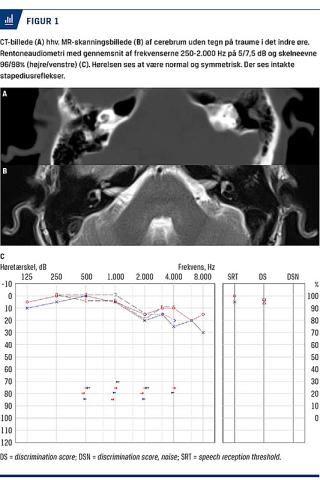

Den objektive vestibulære undersøgelse viste ingen spontannystagmus samt normale resultater af cover-test, impulstest og hovedrysttest. Hørelsen blev fundet normal og symmetrisk ved rentoneaudiometri. Der var intakte stapediusreflekser (Figur 1). Facialisparesen blev ikke vurderet som otogent betinget, men formodedes at skyldes en traumatisk ydre påvirkning. Der blev udført Dix-Hallpike-undersøgelse med patienten liggende på venstre side på et leje, hvilket efter tre sekunders latenstid udløste voldsom svimmelhed og nystagmus, som var svær definerbar. Anfaldet var af 30 sekunders varighed. Dix-Hallpike-undersøgelse på højre side gav negativt resultat.